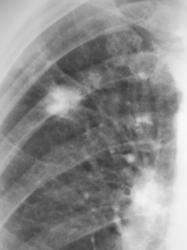

Уважаемые коллеги!. Какие будут мнения по поводу "тени", помеченной стрелкой. Пациент длительное время находился на учёте у фтизиатра.

Если на предыдущих снимках такая же каритнка, то туб изменения в фазе уплотнения. Если нет, то подозрительные спикулоподобные тяжи вселяют подозрения о наличии периферического рака зоне  постуберкулезных изменений или реактивации туб. процесса.

Можно согласиться с предидущим постом. Отложение извести (туберкулома?),но контуры какие-то нечёткие и тяжтстые. Для оценки динамики необходим R-архив.

Валентин Львович! Необходимо дифференцировать с периферическим раком и tbc в стации инфильтрации. Конечно же необходим рентгенархив (если таковой имеется).